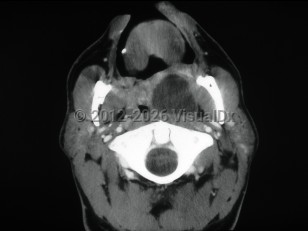

Peritonsillar abscess, also known as quinsy, is a deep neck space infection characterized by a collection of pus in the peritonsillar space.

Patients present with a muffled voice, fever, sore throat, and dysphagia. There is deviation of the uvula to the unaffected side. Trismus and otalgia may be present. This infection usually affects young adults, but all ages can be affected. Older adults may have subtler symptoms. Laboratory findings include leukocytosis. Treatment consists of antibiotic therapy and surgical drainage.